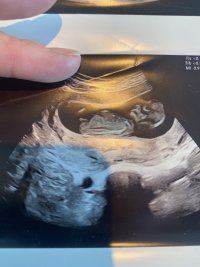

Fra uke 12 kan man se kjønnet ut i fra hvilken vinkel kjønnsorganet står i. Også kalt nub. Jente-nub ligger flatt og gutte-nub står mer oppover. Så legg ut bilder fra uke 12 og oppover så kan vi gjette på hverandres bilder. Dette er mitt 6 svangerskap og har mye erfaring med å tolke ultralydbilder.

Fra uke 12 kan man se kjønnet ut i fra hvilken vinkel kjønnsorganet står i. Også kalt nub. Jente-nub ligger flatt og gutte-nub står mer oppover. Så legg ut bilder fra uke 12 og oppover så kan vi gjette på hverandres bilder. Dette er mitt 6 svangerskap og har mye erfaring med å tolke ultralydbilder.